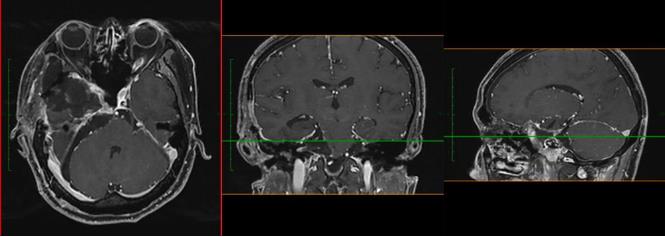

當地醫院對小成頭顱進行MRI檢查,提示:鞍區、中顱窩及后顱窩巨大占位,腦干受壓明顯,且部分已侵襲突破顱底骨質,腫瘤大小約8.2*7.3*5.8cm,此外,電子視野檢查發現右眼鼻側視野、左眼顳側視野嚴重缺損。